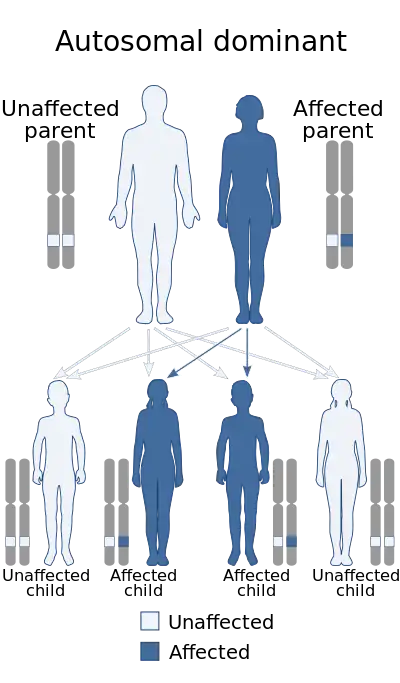

| Buschke–Ollendorff syndrome has an autosomal dominant pattern of inheritance. | |

It is inherited in an autosomal dominant manner.[6][7] Conditions that may appear similar include tuberous sclerosis, pseudoxanthoma elasticum, neurofibroma, and lipoma, among others.[1]